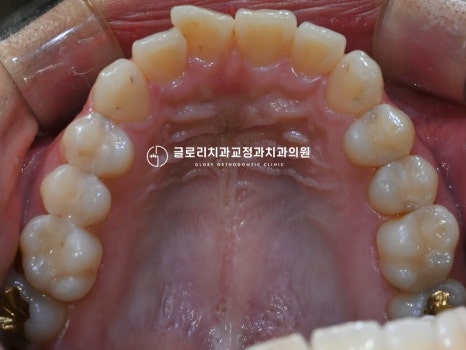

틀어진 앞니가 제자리를 찾아 배열되었으며

전체적으로 봤을 때 훨씬 긴밀하고

고르게 바뀐 것을 확인할 수 있었습니다.

『악궁도 둥근 형태로 더 예뻐진 모습이죠?』